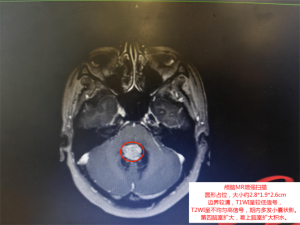

10月26日,王阿姨入院治疗。增强MR扫描结果显示:第四脑室内有一个约2.8cm*1.9cm*2.6cm的类圆形占位。更危险的是,该肿瘤已导致第四脑室扩大,幕上脑室积水——这意味着脑脊液循环被阻断,颅内压力正在不断升高。

第四脑室位于脑干和小脑之间,是脑脊液循环的“交通要道”。一旦被肿瘤阻塞,脑脊液无法正常流动,就会引起“梗阻性脑积水”,导致颅内压急剧升高。 这种情况若持续得不到解除,将压迫脑组织,导致脑功能严重受损,引发意识障碍、昏迷,甚至可能因脑疝形成而在短时间内呼吸心跳停止,直接危及生命。